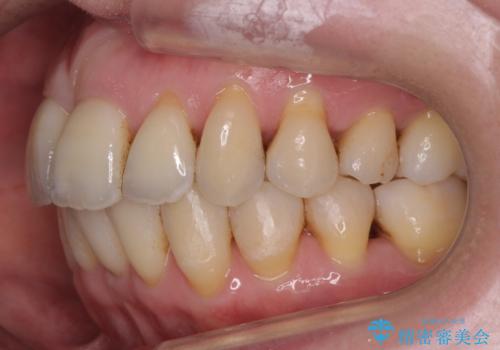

- 前歯の並びを気にして来院。

左下の奥歯が内側に倒れこみ、左上の奥歯は向きが悪くすれ違っていました。

ワイヤー矯正とマウスピース矯正を併用し、左上の位置が悪い歯は抜歯し、左上の親知らずを手前に移動させました。

左上下のかみ合わせが悪く、歯石も多かったため、歯周病の治療も併せて行いました。

難易度の高い部分はワイヤー部分矯正を行うなどして対応し、見える部分はマウスピース矯正を併用する工夫を行いました。